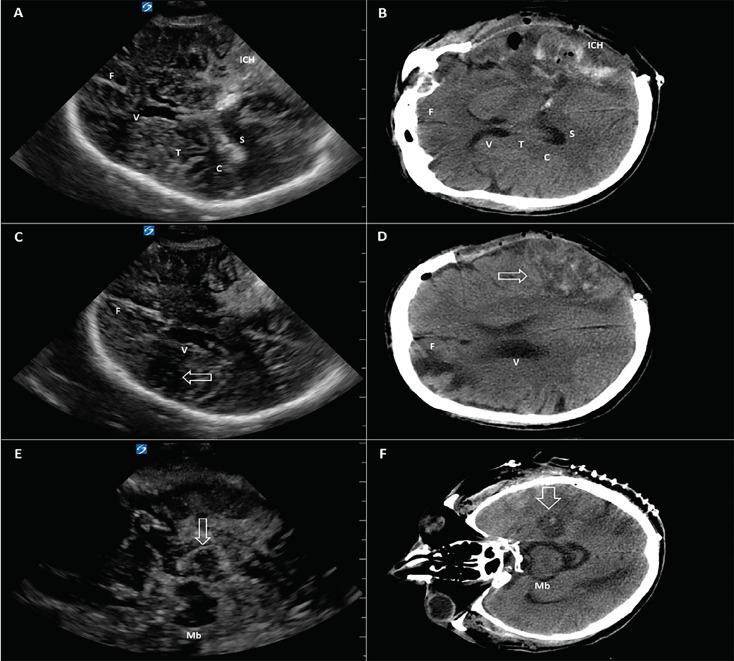

Point-of-care Cranial Ultrasound in a Hemicraniectomy Patient.

Clin Pract Cases Emerg Med. 2018 Sep 10;2(4):375-377. doi: 10.5811/cpcem.2018.7.39379. eCollection 2018 Nov.